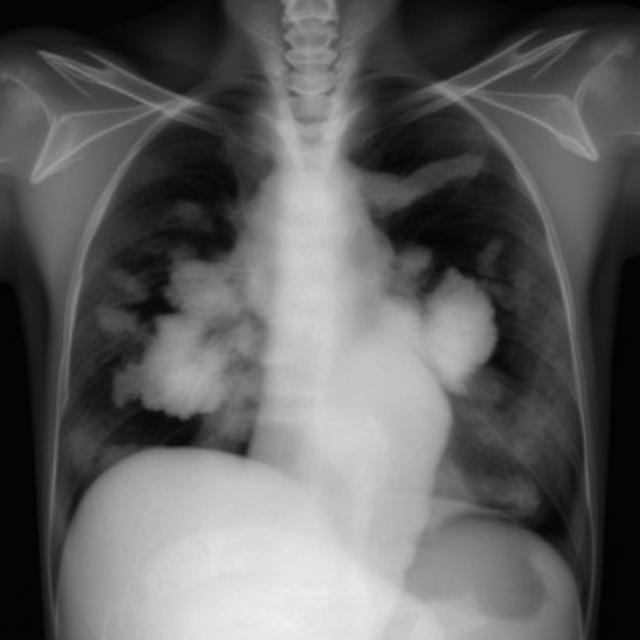

تشخیص به موقع، نقش حیاتی در درمان دارد. پزشک معمولاً از روش‌های زیر استفاده می‌کند:

2. تصویربرداری: رادیوگرافی قفسه سینه یا سی‌تی اسکن برای مشاهده مایع

«با عکس ریه و آزمایش مایع، پزشک دقیقاً فهمید مشکل از قلبم است و درمان مناسب شروع شد.» علی، ۵۰ ساله